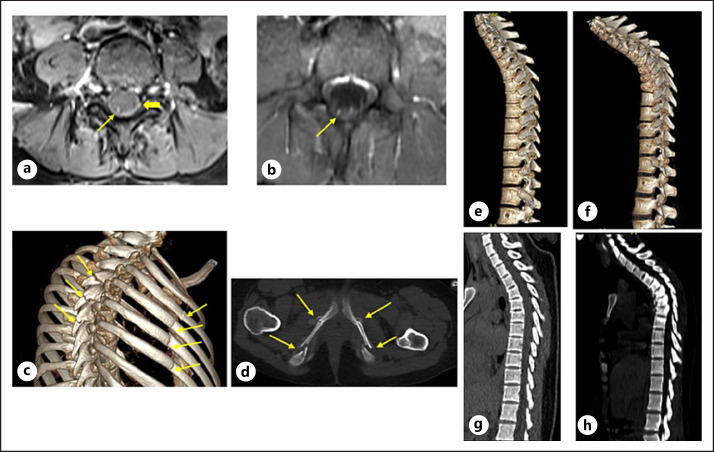

Three weeks later, the patient returned with urinary retention and numbness on both sides of the buttocks radiating down the right leg. Urinary catheterization was performed with a Foley catheter. The spasms of the whole body and limbs had not improved. However, after the spasms, we found abdominal, thigh, and neck rigidity. Spinal MRI with gadolinium contrast media was performed and demonstrated lumbar spinal dural sac and nerve root enhancement (shown in Fig. 1a, b). We also found edema of multiple pelvic muscles, bilateral paraspinal muscles with diffuse hyperintense STIR images (shown in Fig. 2a, b), and multiple thoracic vertebral bodies collapsed from T4-T7 (shown in Fig. 1e-h). Brain MRI was normal. Nerve conduction studies showed normal motor and sensory conduction velocities. Compound muscle action potentials and sensory nerve action potentials were also within NRs. It was impossible to measure the H-reflex and F wave because of muscle spasms caused by stimulation. For the same reason, lumbar puncture and EMG were not able to be performed. Paraneoplastic autoantibodies were tested, using the EUROLINE Paraneoplastic Neurologic Syndromes 12 Ag (IgG). Pulse therapy of corticosteroids at a dose of 1 mg/kg was commenced. Diazepam, gabapentin, and baclofen were administered for symptom relief, and slight improvement was observed. When anti-GAD antibodies with intensity of 91 (+++) and anti-SOX1 antibodies with intensity of 38 (++) were detected, screening for systemic cancer was initiated. 18F-FDG PET/CT showed multiple fractures of the thoracic vertebral spinous process, ribs, sacrum, and pelvic bones (shown in Fig. 1c, d). Avid FDG metabolism was observed in multiple paraspinal and erector spinal muscles in the cervical, thoracic, and lumbar regions. No malignant lesion was detected. Further full blood counts, fasting glucose, and renal and liver function tests were normal. Thyroid hormones, parathyroid hormones, and calcium were within normal limits, except for a high titer of anti-TPO (23.7 IU/mL; NR <5.61 IU/mL) antibody. Protein electrophoresis was unremarkable. The patient refused a Dual Energy X-ray Absorptiometry (DEXA) scan. A multidisciplinary review by a rheumatologist, oncologist, immunologist, endocrinologist, and neurologist determined that there was no evidence of cancer or bone disease.

Fig. 1.

a, b MRI lumbar spine with gadolinium-DTPA demonstrates caudal equine (thin arrow) and dural sac enhancement (thick arrow in A) on axial postcontrast T1W images. c Multiple rib and thoracic vertebral spinous process fractures (arrows) on 3D-volume rendering MSCT images. d Bilateral multiple fractures at the pubic bone (arrows) on axial MSCT bone window. e, f Progressive thoracic spine scoliosis on 3D-volume rendering MSCT images: (e) October 2020 and (f) November 2020. g, h Progressive thoracic spine scoliosis on MSCT MPR sagittal images: (g) October 2020 and (h) November 2020.

Fractures and dislocations are the main complications of SPS [19]. There have been several reports of fractures in SPS patients [18, 20, 21]. Podobinski et al., and Dubow [22] and Jamil et al. [21] reported cases with bilateral hip, scaphoid, or femoral neck fracture. Our patient presented with multiple fractures of ribs, vertebrae, sacrum, and pelvic girdle. The thoracic spine MRI showed vertebral collapse from T4-T7. Osteopenia was seen on the DEXA scan (after 1 month of corticosteroids) with a Z score of −2.5 to −2.6. Thus, the multiple fractures in this patient were likely due to a combination of prolonged, frequent muscle contractions and osteopenia, as CT and PET-CT imaging showed no evidence of specific bone pathology. In addition, thyroid and parathyroid hormones and renal function were normal.